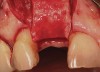

Figure 14  (Case 2) Failed implant at surgical exposure.

Figure 14

Figure 15  (Case 2) Defect after implant removal.

Figure 15